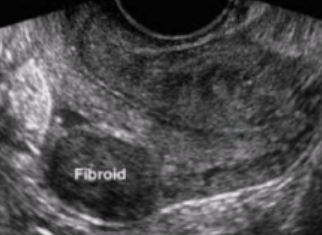

What type of fibroid is depicted in this image?

A. Intramural

B. Submucosal

C. Subserosal

D. Pedunculated

Intramural